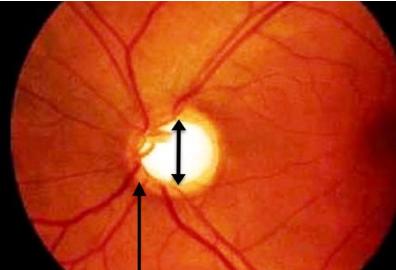

Q.55. A 55-year-old male with a history of hypertension visits the ophthalmology clinic for a routine check-up. On examination, the optic disc shows increased cup-to-disc ratio. The patient denies any visual complaints such as pain, vision loss, or other symptoms. What is the most likely diagnosis?

Correct Answer : C

Q.62. Which of the following suits the most with a glaucoma diagram attached below?

Correct Answer : A